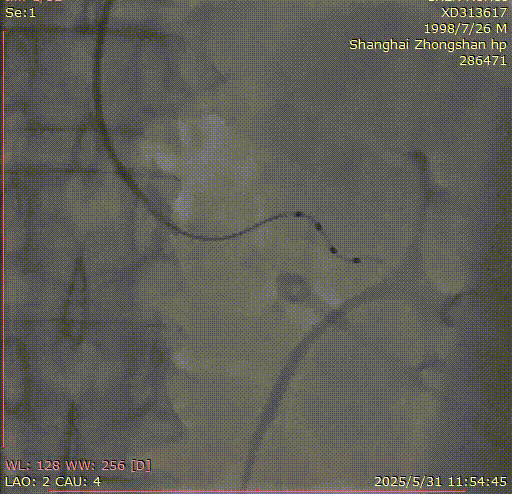

OCC 2025 手术直播|复旦大学附属中山医院成功完成一例经桡去肾神经术(RDN)